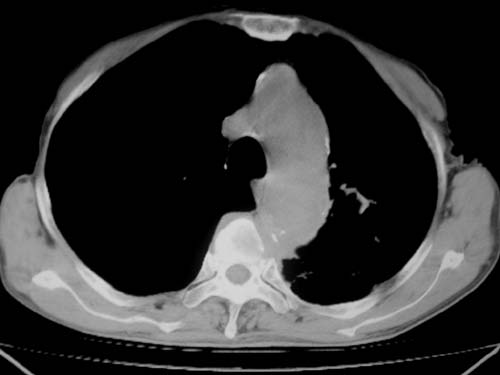

标题: CT19736:男,76岁,咳嗽,胸痛 [打印本页]

标题: CT19736:男,76岁,咳嗽,胸痛

支持左上肺周围型肺癌性并空洞形成伴胸椎转移。

支持 左上肺周围型肺癌性并癌性空洞形成伴胸椎转移。

左上肺周围型肺癌性并空洞形成伴胸椎转移。支持

考虑癌性空洞并胸椎转移。

左上肺癌性空洞伴胸椎转移。